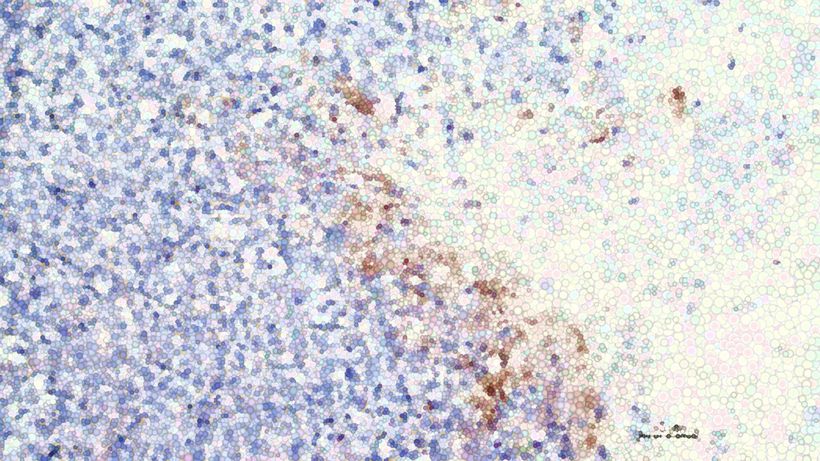

A team of researchers from ChristianaCare and the University of Delaware has uncovered a key early step in how colorectal cancer begins. Their new study shows that a common genetic mutation in colorectal cancer disrupts the colon’s normal tissue renewal process, causing immature cells to build up, tissue structure to break down and early tumors to form. Their findings were published in the journal Cancers. “This finding changes how we think about the very first steps of colon cancer,” said Bruce Boman, M.D., Ph.D., senior author of the study and a senior researcher at the Cawley Center for Translational Cancer Research at ChristianaCare’s Helen F. Graham Cancer Center & Research Institute. “Instead of cancer starting because cells grow too fast, we found that it may start because the normal tissue renewal process slows down, creating a backup of cells that should have moved on. That backup sets the stage for tumors to grow.” The study was led by a multidisciplinary team of engineers, mathematicians, pathologists and tumor biologists from four research institutions. Colorectal cancer is one of the most common and deadly cancers worldwide. According to the World Health Organization, more than 1.9 million people are diagnosed each year, and about 930,000 people die from the disease annually. How healthy colon tissue renews itself The lining of the colon is constantly renewing itself. Every day, billions of cells are shed and replaced to keep the tissue healthy and working properly. This process depends on a steady cycle. New cells form at the base of tiny pockets called crypts, mature as they move upward, and are eventually shed. The new study shows how this natural process breaks down when a mutation occurs in a gene called APC, which is altered in about 90 percent of colorectal cancers. Rather than speeding up cell growth, the APC mutation creates a slowdown, or bottleneck, in the colon tissue’s renewal cycle. According to Boman, this slowdown causes dividing cells to pile up instead of moving through the system as they should. The result is a kind of tumor cell “traffic jam” that leads to distorted tissue and the formation of adenomas, early growths that can become cancerous. What APC-mutant tissue looks like To see these changes up close, the team compared healthy colon tissue with tissue from patients who have familial adenomatous polyposis, or FAP, an inherited condition caused by APC mutations. The differences were clear: APC-mutant crypts contained more immature, rapidly dividing cells. Fewer cells matured into specialized cells needed for healthy tissue. The zone where cells divide extended higher than normal. The overall renewal cycle took longer. “These findings are significant because they show how cancer-driving mutations change tissues that normally renew themselves nonstop,” Boman said. Pairing patient tissue with computer modeling To see how these changes happen over time, the researchers studied patient tissue and used a computer model that shows how colon cells normally grow and renew. When they slowed this renewal process in the model, it matched what they saw in tissue with the APC mutation. Cells became crowded, the structures lost their normal shape, and early tumor-like growths, known as adenomas, began to form. This confirmed that delayed renewal alone can trigger the earliest changes linked to colon cancer, even before cells appear abnormal under a microscope. “Our findings show that APC mutation does more than turn on growth signals,” Boman said. “It changes the timing of renewal. Once that timing is off, the tissue becomes vulnerable to structural damage and early tumor growth.” Building on earlier research This study builds on earlier work by the same team that mapped how healthy colon tissue renews itself. In prior studies, the researchers identified five basic biological rules that guide how colon cells grow, move and replace one another in a steady, organized way. The new findings show what happens when that system breaks down. A common mutation called APC slows the normal renewal process. Young, stem-like cells begin to build up before they can mature. Over time, that imbalance creates the conditions for early tumor growth. To pinpoint how these changes unfold, researchers Gilberto Schleiniger, Ph.D., and Christopher Raymond, Ph.D., from the University of Delaware’s Department of Mathematical Sciences paired mathematical models with real patient tissue data. Their work shows that even small delays in cell renewal can push healthy tissue toward cancer. “This gives us a clearer picture of how cancer can start long before a tumor is visible,” said Schleiniger. “By understanding the rules that keep healthy tissue in balance, we can see where and how things begin to go off track.” A possible path toward future treatments The findings also point toward a potential new approach to treatment. The researchers found evidence that the disrupted renewal process may trigger a chain reaction that allows pre-cancerous cells to keep copying themselves and fueling tumor growth. By targeting this process, it may be possible to restore normal renewal timing and healthier tissue structure before cancer becomes established. “This study shows that cancer isn’t just about rogue cells, but about a system that’s fallen out of rhythm,” said Bruce Boman, M.D., Ph.D. “If we can reset that renewal process, we may be able to prevent or slow early tumor growth before it gains momentum.”